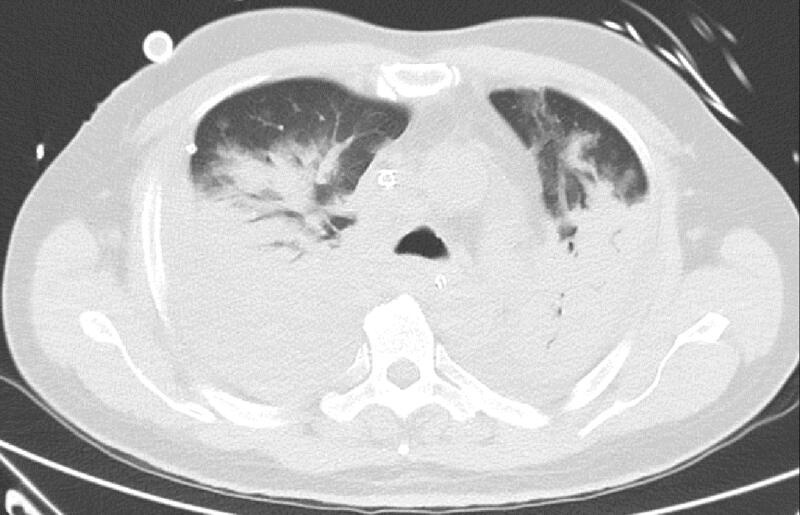

CT scan phổi cho thấy phổi của ông Kiat bị viêm và chứa đầy chất lỏng. Ảnh: Straistimes.

Ông được đưa vào Bệnh viện Khoo Teck Puat (KTPH) vào ngày 12/3 và xác nhận dương tính với SARS-CoV-2 vào chiều cùng ngày. Hai ngày sau, ông Kiat được đặt nội khí quản do nồng độ oxy trong máu ngày càng xấu đi.